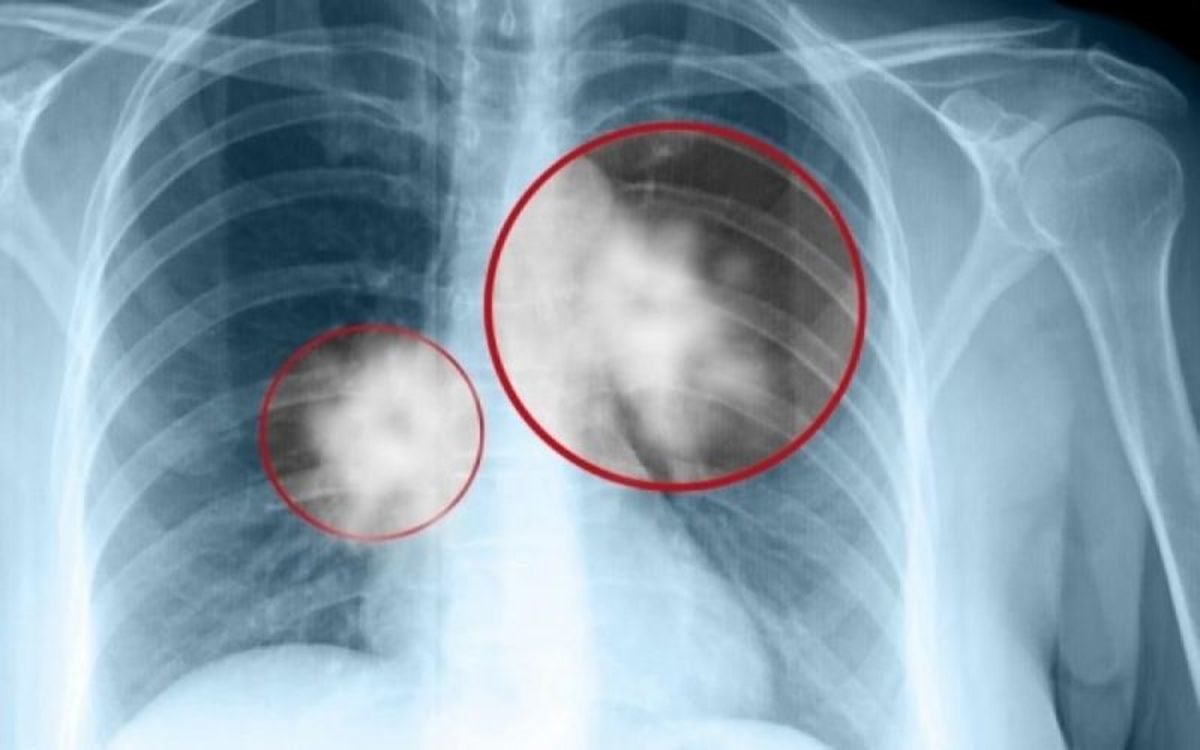

Νέα θεραπεία πρώτης γραμμής για τον προχωρημένο μη μικροκυτταρικό καρκίνο πνεύμονα

Η Novartis λαμβάνει θετική γνωμοδότηση από την Επιτροπή Φαρμακευτικών Προϊόντων για Ανθρώπινη Χρήση (CHMP) για τη χρήση του Ceritinib ως θεραπεία πρώτης γραμμής σε ALK θετικό προχωρημένο μη μικροκυτταρικό καρκίνο του πνεύμονα (ΜΜΚΠ).

Η Novartis ανακοίνωσε ότι η Επιτροπή Φαρμακευτικών Προϊόντων για Ανθρώπινη Χρήση (CHMP) του Ευρωπαϊκού Οργανισμού Φαρμάκων (EMA) συνέστησε την έγκριση της επέκτασης της χρήσης του Ceritinib (σεριτινίμπη), ώστε να περιλαμβάνει τη θεραπεία πρώτης γραμμής των ασθενών με προχωρημένο μη μικροκυτταρικό καρκίνο του πνεύμονα (ΜΜΚΠ), οι όγκοι των οποίων είναι θετικοί στην κινάση αναπλαστικού λεμφώματος (ALK+). Εάν λάβει έγκριση, το Ceritinib θα αποτελεί μια νέα θεραπευτική επιλογή για τους ασθενείς που δεν έχουν λάβει προηγούμενη θεραπεία και τους νεοδιαγνωσθέντες ασθενείς με ALK+ προχωρημένο ΜΜΚΠ.